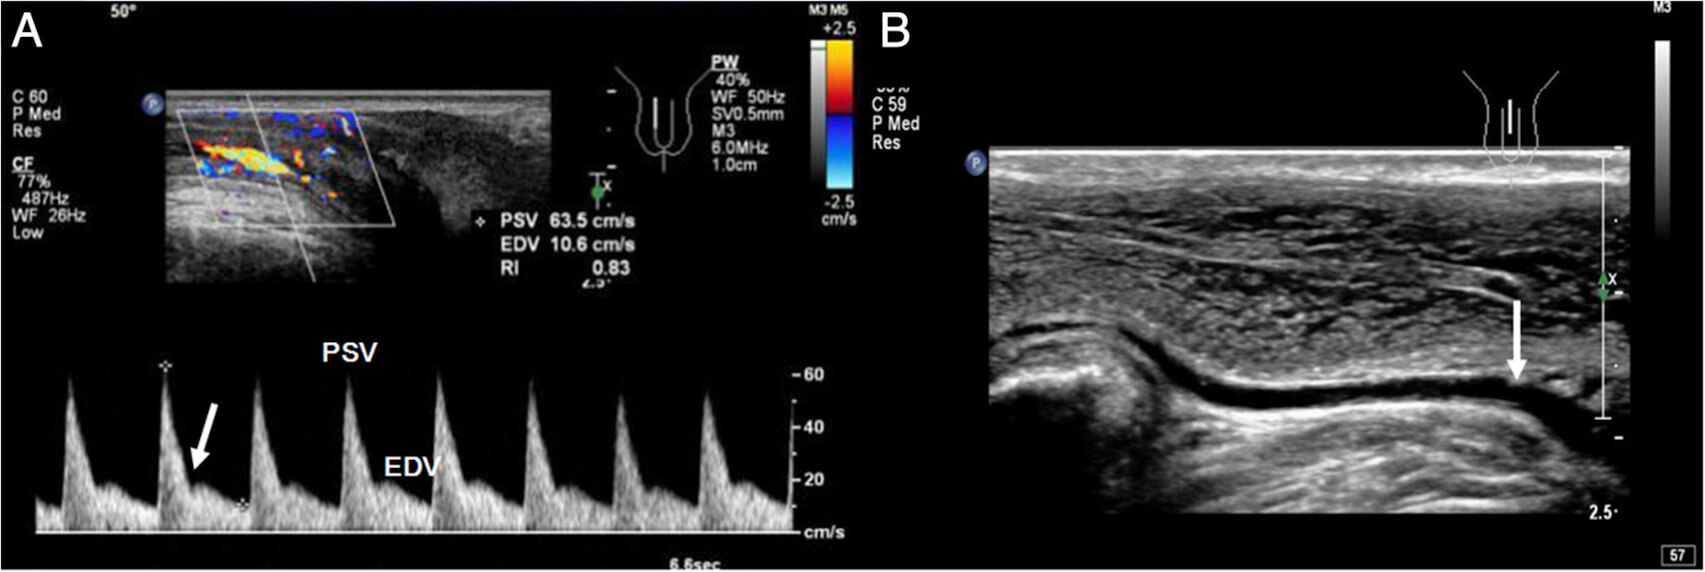

- Ecografie de penis, cu rolul de a evalua circulatia sangvina la nivelul penisului, afectarea acesteia fiind una dintre cele mai frecvente cauze ale disfunctiilor erectile

Ecografia Doppler de penis. Cand este necesara?

Ecografia Doppler de penis este o procedura care este utilizata pentru:

- a evidentia tulburarile circulatorii la acest nivel si permite medicului urolog sa se documenteze daca aveti un tip de disfunctie erectila

- a prezice raspunsul disfunctiei erectile la tratamentele si medicamentele vasodilatatoare care imbunatatesc fluxul de sange catre penis.

Cum se efectueaza ecografia Doppler de penis?

Ecografia se va efectua in timp ce stati intins pe spate pe masa de examinare. O injectie la nivel penian a unui agent vasodilatator numit Trimix va fi efectuata folosind un ac foarte mic. Acest lucru va va ajuta sa relaxati muschii erectili din penisul dvs., sa va dilatati arterele penisului. Aceasta va duce la o crestere a fluxului de sange catre penis si va va oferi o erectie. Majoritatea oamenilor experimenteaza doar o mica senzatie de intepatura odata cu injectia.

Folosind o mica sonda cu ultrasunete, plasata de-a lungul axului penisului, vom masura fluxul de sange din artera penisului pe ambele parti ale penisului. Nu exista nicio durere implicata in aceasta portiune a procedurii.

CITESTE MAI MULTEcografia Doppler de penis

Controlul periodic este cheia pentru mentinerea sanatatii aparatului uro-genital. O ecografie Doppler de penis facuta o data pe an in cadrul consultului urologic, ajuta la diagnosticarea din timp a anumitor afectiuni si creste sansele de vindecare.